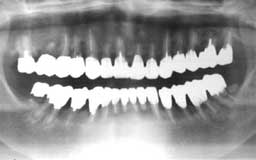

Nさん 初診時 51歳 女性

10年以上前からメインテナンスを受けていたということで、治療済みの歯や虫歯が多いもの の、歯周組織の状態は良好

Nさん 20年後 71歳

金属の被せが非常に目立ちますが、28本すべて健在は立派です